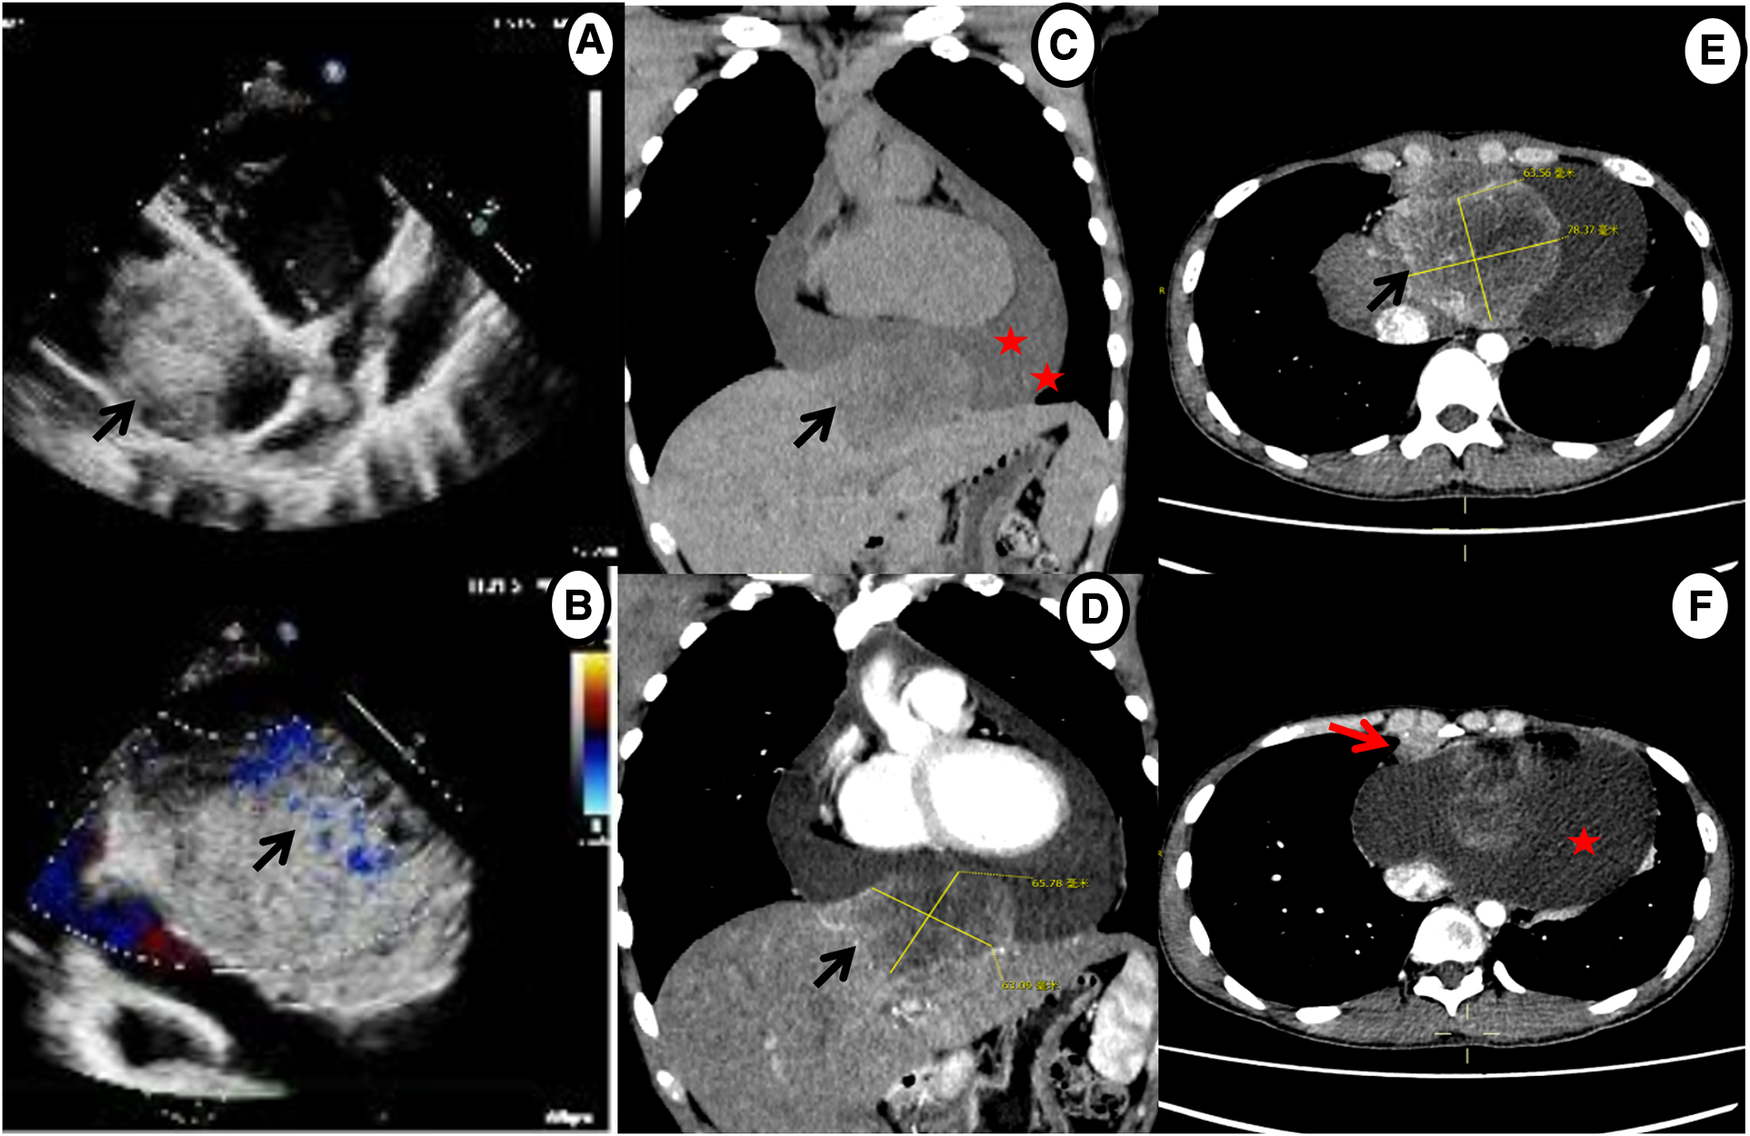

Given his unusual symptoms and laboratory results, transthoracic echocardiography (TTE) and chest contrast-enhanced computed tomography (CT) were recommended. The TTE revealed a heterogeneous isoechoic pericardial mass with massive pericardial effusion (Figure 1A). Color Doppler flow imaging demonstrated minimal blood flow signals along the margins of the mass (Figure 1B). The dimensions of the atria and ventricles appeared to be within the normal range, and the morphology and function of the cardiac valves were unremarkable. The CT scan revealed a 6.5 cm × 7.8 cm × 6.3 cm irregular mass between the pericardium and diaphragm and significant pericardial effusion (up to 40 mm) (Figures 1C–E). Additionally, a 1.0 cm enlarged lymph node was detected in the right cardio-diaphragmatic angle (Figure 1F).

Figure 1. Echocardiography and chest contrast-enhanced CT demonstrating a massive mass (black arrow) and pericardial effusion (star). (A,B) Echocardiography shows a mass in the pericardium with a small amount of blood flow signals. (C–E) CT reveals an irregular, heterogeneously enhancing mass between pericardium and diaphragm with massive pericardial effusion. (F) Axial contrast-enhanced CT shows enlarged enhancing lymph nodes in the right cardio-diaphragmatic angle (red arrow).